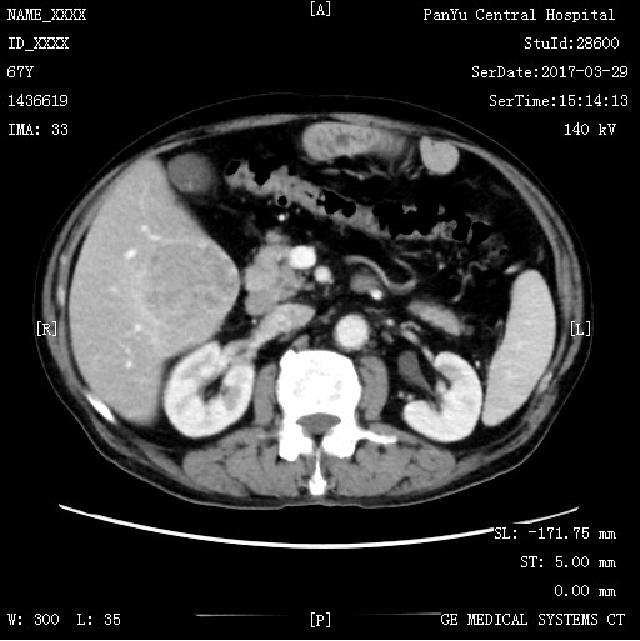

影像学检查:

CT:肝S5肝细胞癌,大小约55×68×55mm,有假包膜,另胆囊结石

动脉期:

静脉期: